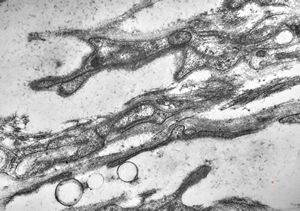

F,13y. | n.suralis … axonal neuropathy … Charcot-Marie-Tooth disease

Demyelinized nerve with bands of Büngner (square, inset) . P- perineurium, | E - epineurium. (Human, sural nerve.) Scale 0.2 mm.